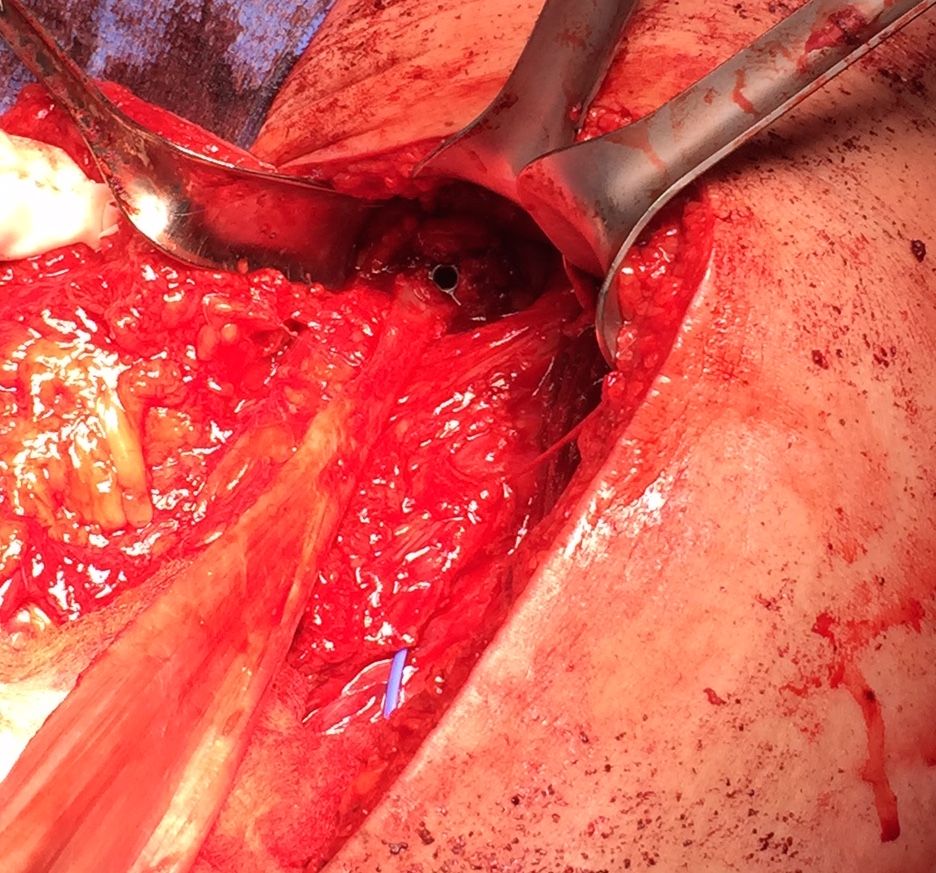

Identify and release sciatic nerve

Release hamstring

- see if hamstring will reach

Sciatic nerve with blue vessiloops

Prepare allograft

- tendo achilles

- 9 x 20 mm bone block

- drill to 10 x 25 mm tunnel using ACL instruments

- ensure that beath pin does not advance

- secure with 7 x 20 mm screw, bone typically very strong

Ischial tuberosity exposed, then achilles bone block secured with screw

Pulvetaft weave tendon through the strongest, thickest part of the stump